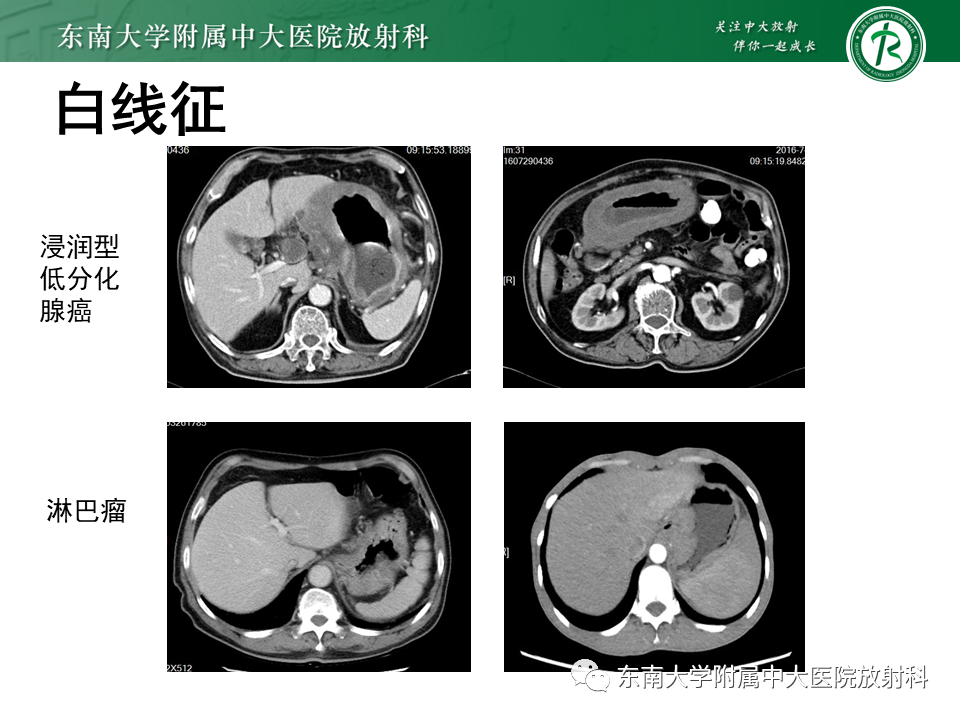

胃黏膜相关淋巴组织(MALT)淋巴瘤